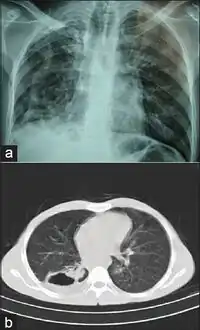

The first strains of M. branderi were isolated from samples obtained from nine patients, some of whom had cavitary mycobacteriosis of the lungs that was resistant to available drugs. In most cases, repeat samples obtained from each patient were positive for acid-fast bacilli as determined by microscopy, and the only cultivable species was M. branderi. M. branderi has to be considered a potential human pathogen.